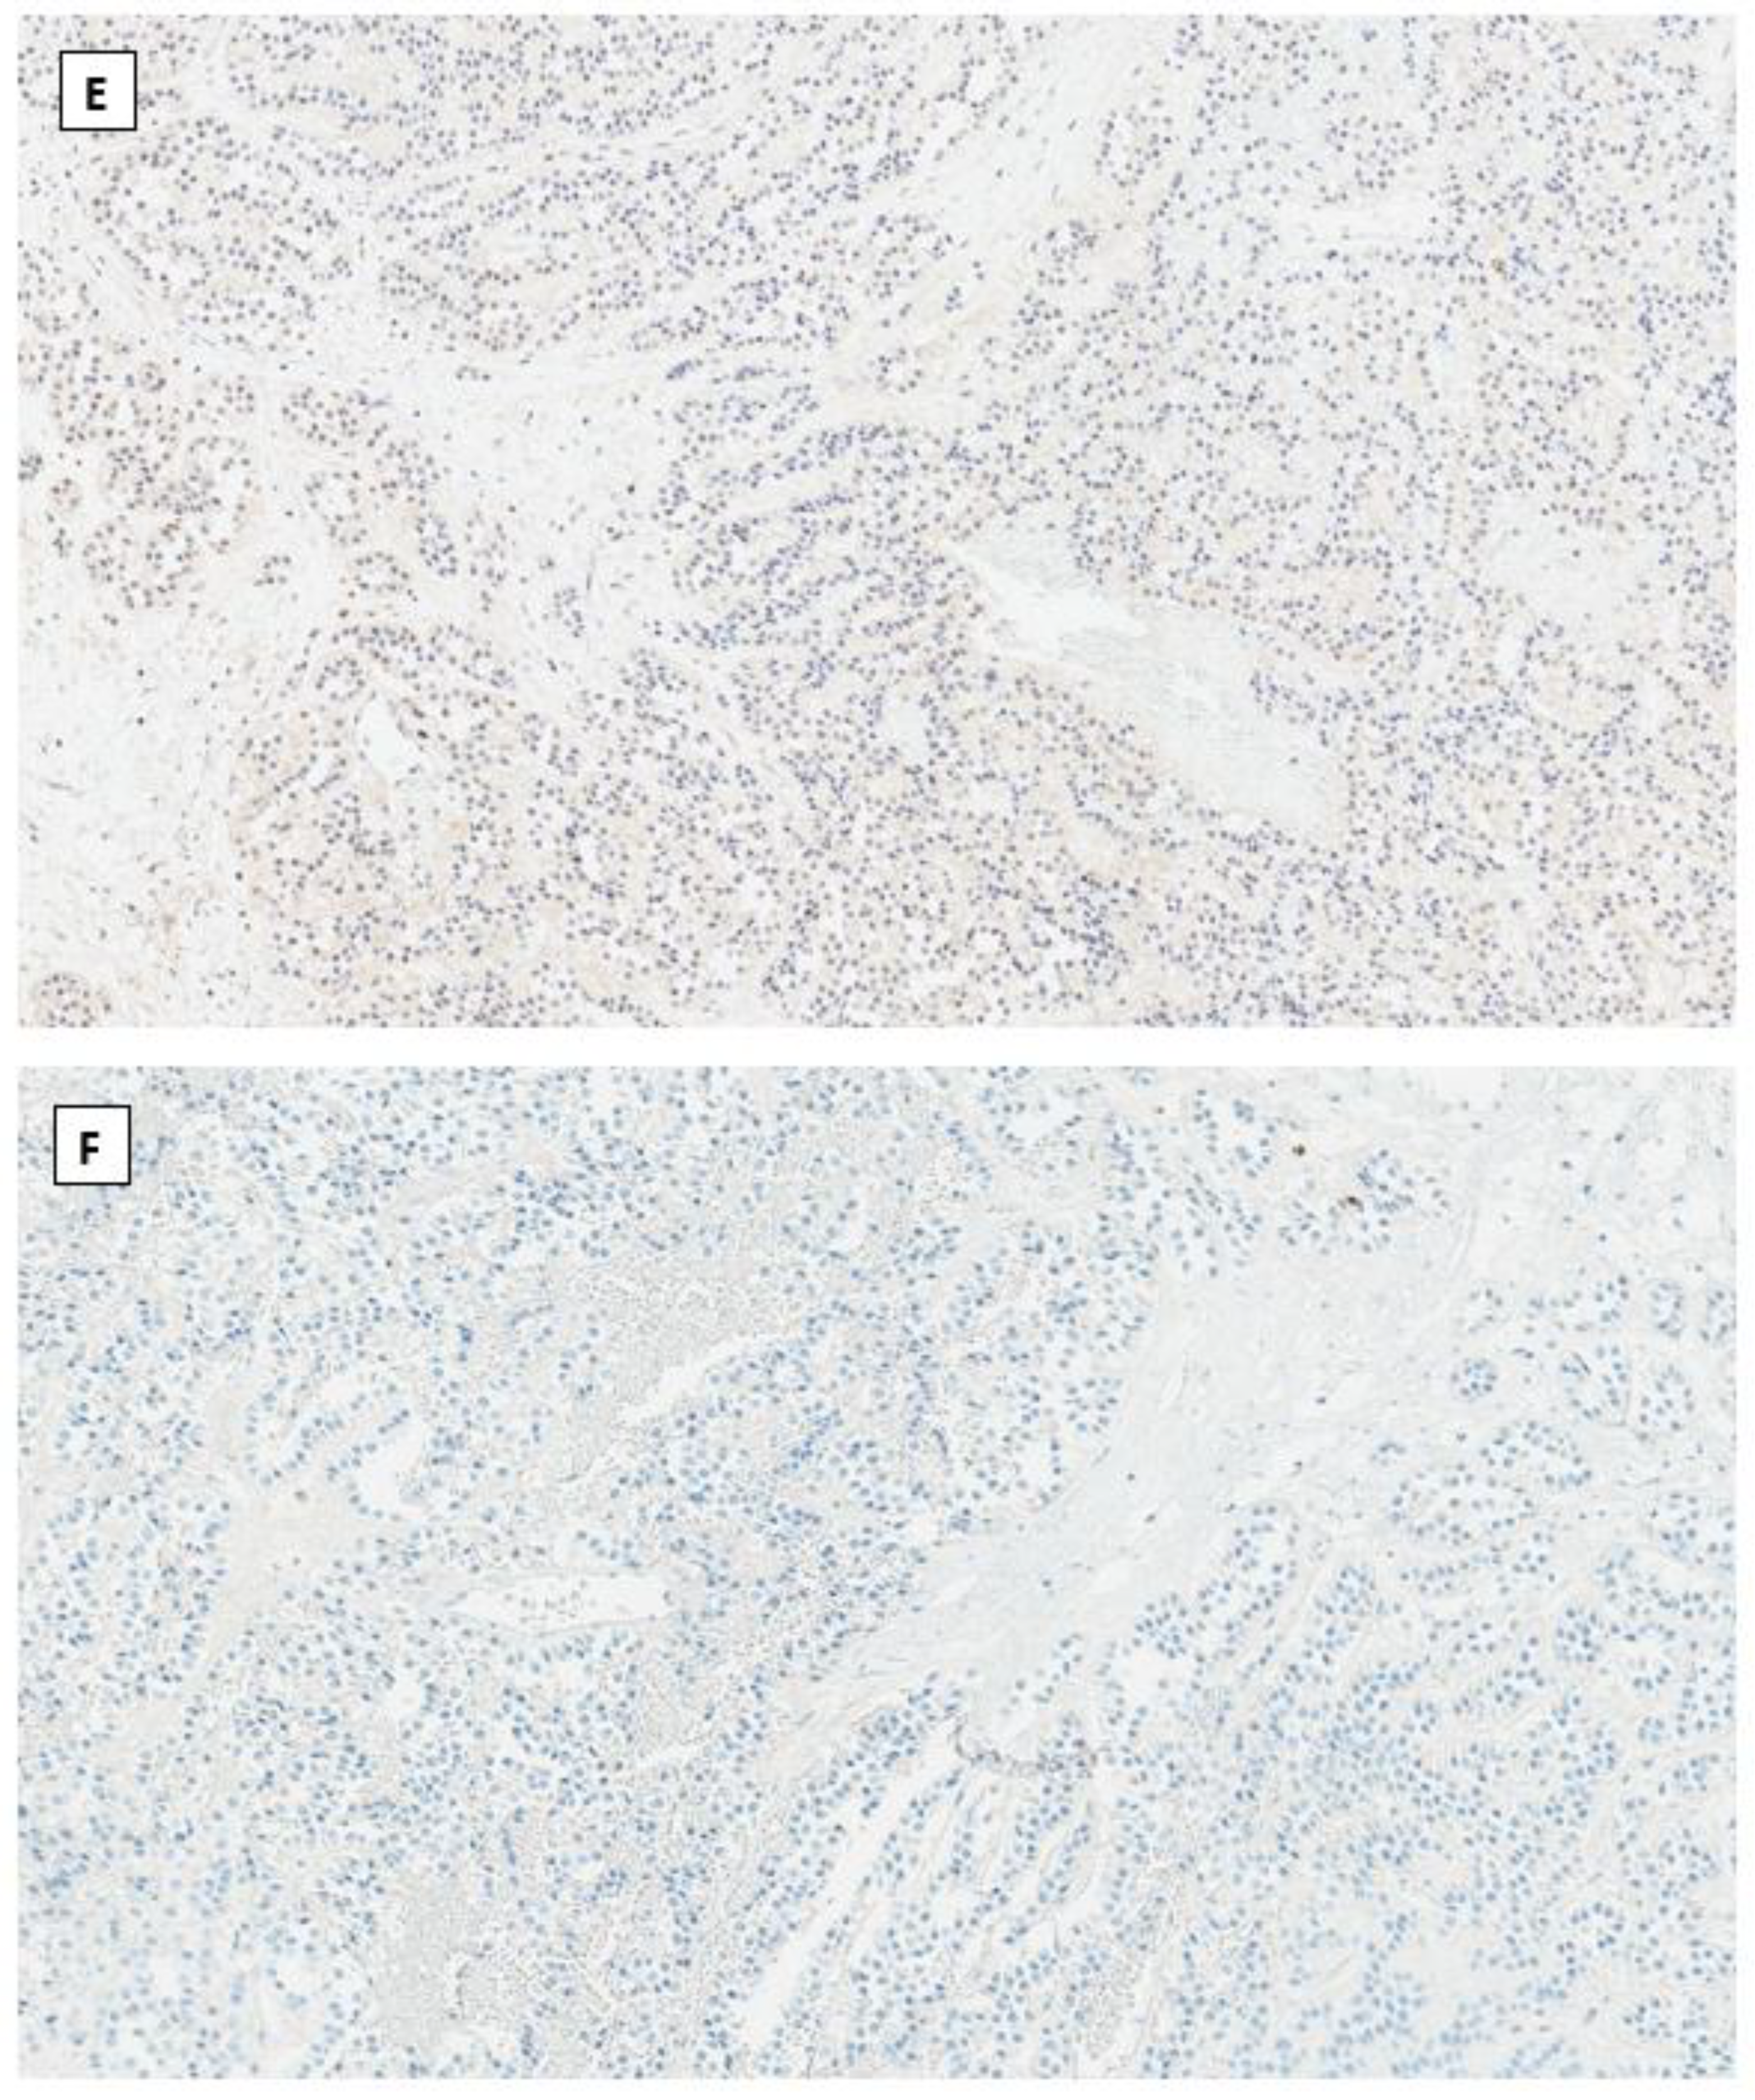

4.1. Solid Pseudopapillary Neoplasm (SPPN)

4.2. Microcystic Stromal Tumor (MCST)

4.4. Immunohistochemical Phenotype Shared in Ovarian Low-Grade Stromal Tumors